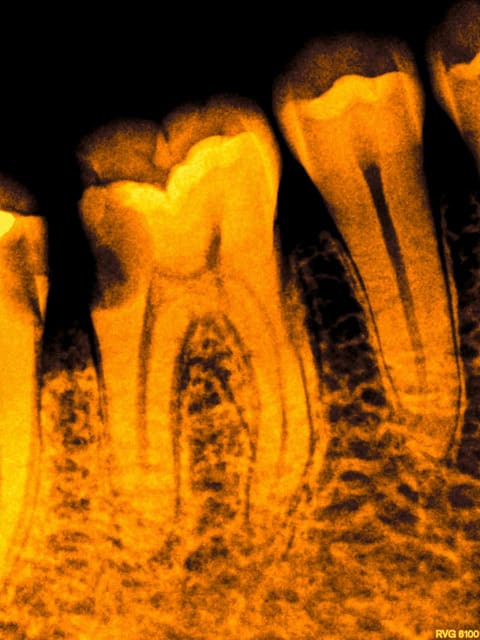

exemple :

Mobilité 31 (motif de la consultation); plan d'occlusion HS ( égression ).

Patient n'ayant pas 10 balles (mais qui travaille pourtant mais au smic malgré la moitié de cotisations sociales il a peanuts de remboursements) avec une mutuelle de merde en plus.

Amusez vous bien.

Endos + raser le secteur postérieur haut, rétablissement d'un plan d'occlusion correct avec de la fixe + Stellite bas.

Ca durera bien quelques années.

Douleur froid secteur 4. Bilan radio ( coté 6 radios, fuck le pano pas indiqué en plus source d'emmerdes-))))) détartrage.

C'est sur. 1H pour 2 endos molaires c'est chaud, on finit par faire des conneries-))))

En espérant qu'ils soient en Y comme la 7.

Faivre-rampant

les endos sont chouettes.

je suis encore pour ma part pas mal long quand il s'agit d'endo.

sinon c'est quoi le truc entre la 5 et la 6.

Wed jet. Ca se pose avec une pince.

R25 + digue ca fait gagner du temps. Ceci dit dans ce cas j'ai un peu grillé les étapes ( forcé) D'ou le faux canal sur le ml de 46.

Trop fort mon Chicot! Même la radio sépia, les photos et le faux canal sont beaux!

Une heure pour celle là , comme quoi, ca varie....